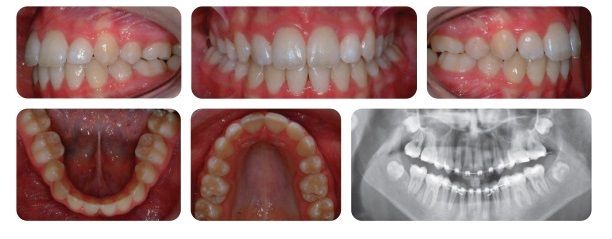

Sau khi tháo niềng, bệnh nhân có nụ cười đẹp, tự tin. Răng thẳng đều, không còn tình trạng chen chúc hay hô vẩu. Răng hàm trên và hàm dưới được lồng múi tối đa. Tương quan khớp cắn trở về loại I.